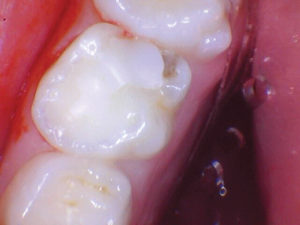

Caso 2

Un nuevo paciente de 7 años presentó una importante descomposición e hipocalcificación en el primer molar permanente superior derecho. Durante mucho tiempo se ha demostrado que los primeros molares permanentes cariados e hipocalcificados en pacientes pediátricos le dan al profesional un dilema restaurador difícil. ¿Deberíamos intentar prepararnos y restaurarlos conservadoramente? ¿Deberíamos ser más agresivos y restaurar con una cobertura completa como una corona de acero inoxidable bien adaptada? Activa proporciona una gran alternativa en estos casos, con liberación de calcio, fosfato y fluoruro junto con alta resistencia y resistencia a la fractura.

Figura 1. Después del ataque ácido y el uso del agente de unión Scotchbond Universal (3M), los dos molares primarios superiores se restauraron con Activa Bioactive Restorative A2. |

Figura 2. Una vez que se excavó la descomposición y se colocaron los márgenes en superficies sólidas, se colocó un bisel pesado en el esmalte para aumentar la resistencia de la unión y la integridad marginal. El área oscura central era sólida. El diente estaba revestido con una base / revestimiento Activa. |

Figura 3. Después del grabado selectivo y el uso de Scotchbond Universal, el diente se restauró con Activa Restorative A2. |

Figura 4. El seguimiento de 18 meses no mostró fracturas y márgenes intactos. |